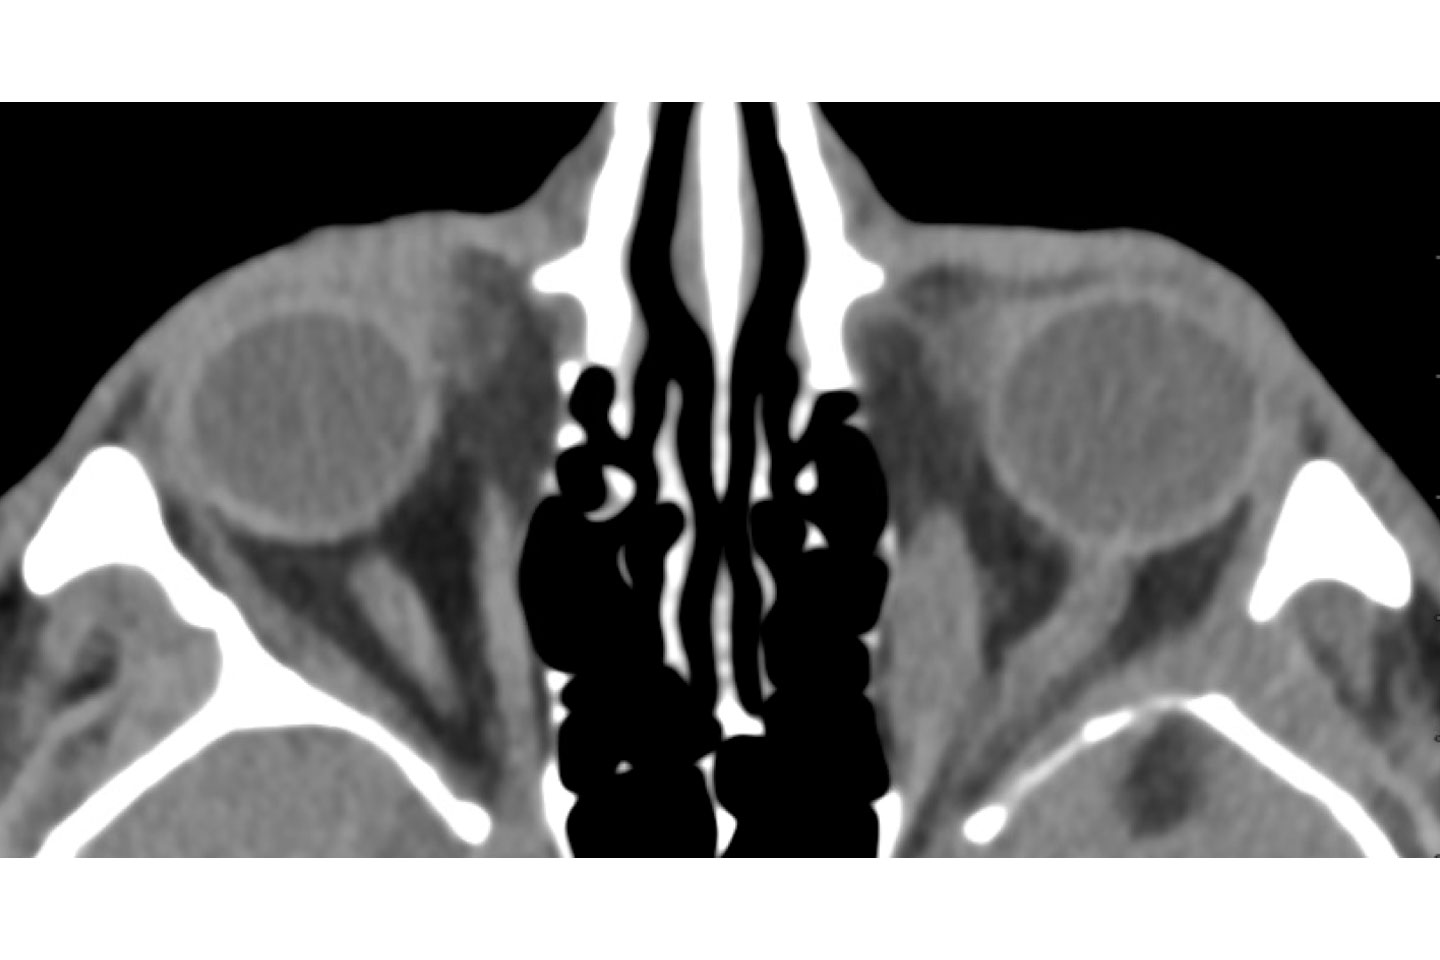

Axial orbital imaging prior to orbital decompression and teprotumumab infusion shows left-sided exophthalmos and enlargement of the left superior rectus. Source: NYU Langone Health